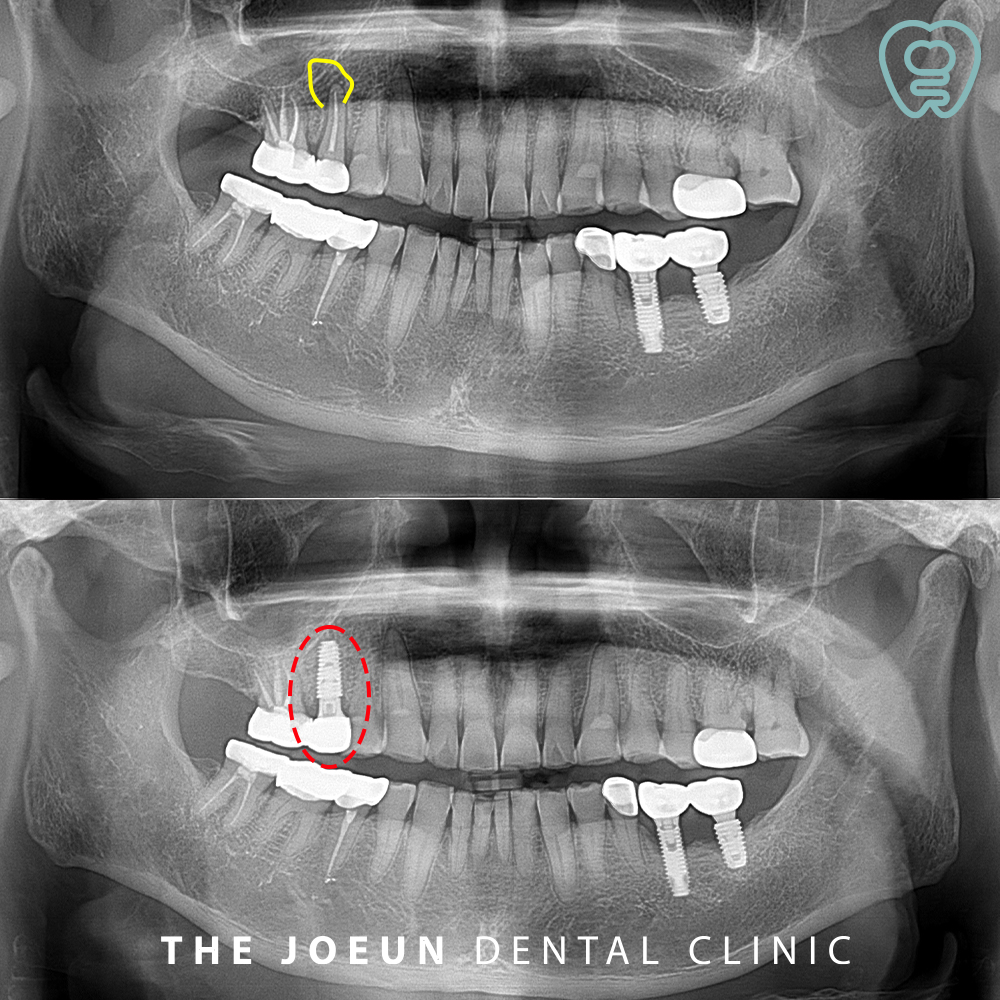

오늘은 뿌리 끝 염증이 있는 치아를 발치한 후 즉시 임플란트 식립을 진행하신 환자분을 소개해 드리도록 하겠습니다.

환자분께서는 오래 전 씌워두었던 오른쪽 위 어금니 부위가 조금 찝찝한 느낌이 드신다며 검진을 위해 내원해 주셨는데요. 외관상으로는 큰 문제가 없어 보였지만 두번째 작은 어금니의 뿌리 끝으로 커다란 염증이 관찰되고 있었습니다. 이미 신경치료 후 크라운이 되어 있는 치아로 발치 후 임플란트를 진행하기로 계획을 수립하였습니다.

이미 치아가 부서져 조각조각 말끔히 발치를 한 후, 바로 임플란트 식립을 진행하였는데요. 식립에 앞서 반드시 정밀 치과 진단을 통해 구강 상태를 확인하고 정석적인 치료 계획을 세울 수 있어야 합니다. 이 과정에서 CT 촬영과 구강 스캐너를 활용해 신경과 혈관 등 주변 조직의 위치, 치아와 잇몸뼈의 상태에 대한 데이터를 활용하는 것이 중요합니다.

기존의 잇몸뼈와 단단하게 융합할 수 있도록 약 3개월 정도 후에 최종 보철물까지 완료하였습니다.